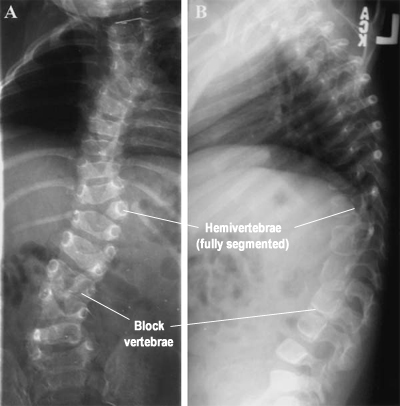

الفقرة النصفية هي تشوه خلقي في الفقرات يحدث خلال مرحلة نمو الجنين داخل الرحم، حيث لا يكتمل نمو أحد جانبي الفقرة. يؤدي هذا الخلل إلى وجود فقرة غير متساوية، مما يسبب انحناء جانبي في العمود الفقري ويؤثر على توازنه واستقامته. في كثير من الحالات، تكون هذه الفقرة هي السبب الأساسي في تطور الاعوجاج الخلقي للعمود الفقري.

الاعوجاج الخلقي (Congenital Scoliosis) هو انحناء جانبي غير طبيعي في العمود الفقري يظهر منذ الولادة. قد يكون ناتجًا عن فقرة نصفية واحدة أو أكثر، أو تشوهات أخرى في تكوّن الفقرات. يختلف هذا النوع من الجنف عن الجنف المكتسب، لأنه مرتبط بخلل في التكوين البنيوي للفقرات.

الأشعة السينية: تكشف شكل الفقرة النصفية وشدة الانحناء.

الرنين المغناطيسي أو الأشعة المقطعية: تُستخدم للكشف عن تفاصيل إضافية مهمة، خاصة قبل اتخاذ قرار جراحي.